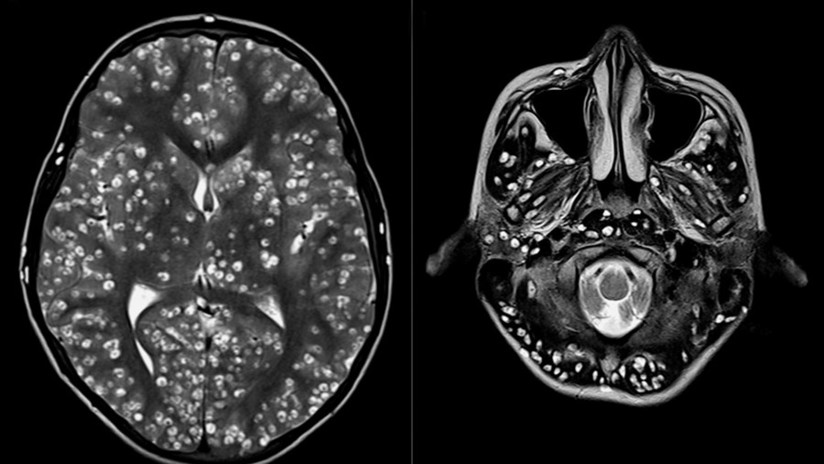

Tras practicarle una resonancia magnética y exámenes de ultrasonido, los especialistas encontraron que la corteza cerebral y el tronco encefálico del paciente estaban llenos de larvas.

Médicos indios descubrieron el cerebro de un joven de 18 años plagado de quistes causados por un parásito porcino. El muchacho, al que los doctores no pudieron salvarle la vida, acudió al servicio de urgencias de la ciudad de Faridabad, en el estado de Haryana, aquejado de fuertes dolores de cabeza y convulsiones.

El muchacho padecía neurocisticercosis, una enfermedad parasitaria originada cuando una persona ingiere huevos microscópicos de una tenia porcina y que afecta al tejido muscular. De ahí los parásitos se propagan al cerebro. Los personas infectadas pueden pasar mucho tiempo sin presentar síntomas.